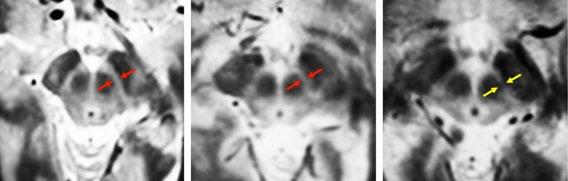

MIT neuroscientists imaged the substantia nigra in a young adult, left, an older adult, center, and a Parkinson’s patient, right. They found that the substantia nigra deteriorates in Parkinson’s patients.

To overcome that, the MIT team used four types of MRI scans, each of which uses slightly different magnetic fields, generating different images. By combining these scans, the researchers created composite images of each patient’s brain that clearly show the substantia nigra and basal forebrain. “Our new MRI methods provide an unparalleled view of these two structures, allowing us to calculate the precise volumes of each structure,” Ziegler says.

After scanning normal brains, the researchers studied 29 early-stage Parkinson’s patients. They found significant loss of volume in the substantia nigra early on, followed by loss of basal forebrain volume later in the disease, as predicted by Braak.